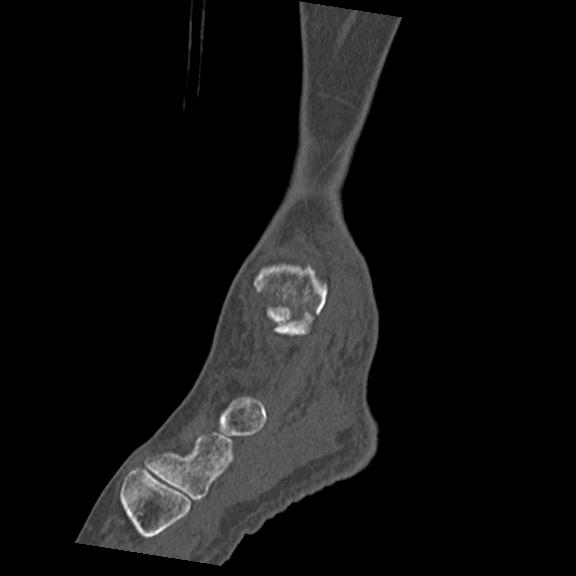

56476 8/28 4R 1/21 2R 左足関節 デジカメ写真 72歳女性 右足関節AS